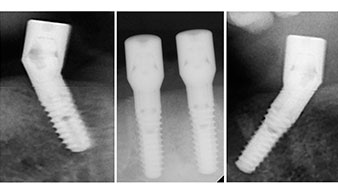

A three-dimensional cone beam computed tomography scan (CBCT, Planmeca) was performed to aid planning and minimize risks. This revealed that the quality and quantity of the available bone were sufficient for the surgery and immediate restoration using the Fast & Fixed method. Following the protocol for this concept, the implants are inserted at 35, 32, 42 and 45. Angling the distal implants by up to 45° shifts the emergence profile to posterior and generates a larger support polygon (Fig. 3).

The surgical protocol for the implants employed (SKY, bredent medical) specifies a speed of 1,200 rpm for the pilot drilling (Fig. 7 - 9).

This corresponds to the next preset position in the Implantmed. Here we see the W&H contra-angle handpiece being held at a 45° angle to mesiocaudal in the region of 45 in order to preserve the mental nerve. The mental foramen is used as the anatomic reference for all drilling in this region. The subsequent holes were drilled at a reduced speed of 300 rpm (Fig. 10 and 11).

The next programmed setting is already for placement of the implants. In our practice we usually employ a torque of 32 Ncm to place the implants (Fig. 12 and 13).

High primary stability is an absolute requirement for an immediate restoration. In order to achieve this, the hole was not tapped in this case. The W&H Implantmed drill unit used here is equipped with a suitable special mode for this, which can also be directly selected and is indispensable for many indications. The final revolutions when placing the implants exceeded the value of 32 Ncm and were performed by hand. In such cases, we recommend utilizing the implants’ self-tapping function and twisting the implants backwards and forwards several times. This allows the implant to approach the final position gradually without exerting excessive pressure on the bone (Fig. 14).

Angled abutments (35°) were screwed in to compensate for the divergence of the distal implants, with the result that the emergence profile of all implants was as perpendicular as possible to the bite plane. This is a prerequisite for occlusal placement of the provisional and subsequently the permanent denture (Fig. 15 and 16).

The light increases the contrast in the oral cavity and improves visual perception. Both the contra-angle handpiece and the S-11 straight handpiece from W&H are externally cooled, which can be seen as a great advantage because the saline solution arrives exactly where it’s needed and can also be subsequently adjusted if necessary. The contra-angle and straight handpieces can be dismantled, which is highly recommended for hygiene and sterilizability. Four SKY implants measuring 4.0 x 14mm were placed.